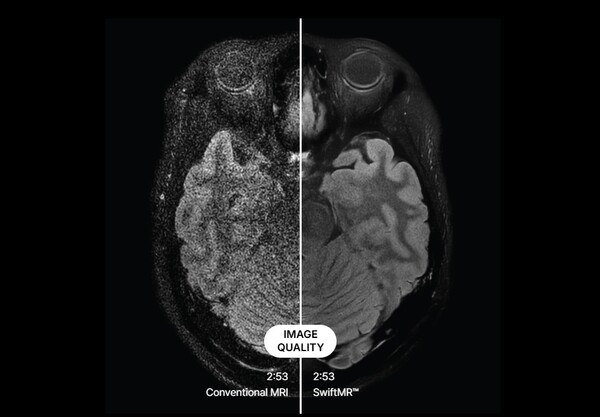

• 전통적인 MRI 촬영 영상(왼쪽)과 SwiftMR로 노이즈를 제거한 영상(오른쪽) 비교. /에어스메디컬

▲ 전통적인 MRI 촬영 영상(왼쪽)과 SwiftMR로 노이즈를 제거한 영상(오른쪽) 비교. /에어스메디컬

에어스메디컬의 기술이 주목받는 이유는 단순히 촬영 시간을 줄이는 것을 넘어선다. 가장 큰 차별화 포인트는 25~30년 된 구형 MRI 장비도 업그레이드할 수 있다는 점이다.

박 CFO는 “일반적으로 MRI 장비의 평균 수명은 13년 정도”라며 “하지만 우리 소프트웨어를 사용하면 최대 20년까지도 사용할 수 있다”고 말했다. 이어 “중고 MRI 장비의 이미지 품질 손실을 AI로 보완해 장비 수명을 연장할 수 있기 때문”이라고 덧붙였다.

이는 지멘스, GE, 필립스 등 대형 제조사들의 AI 솔루션과는 다른 접근법이다. 제조사들의 AI는 자사 신규 장비의 10~40% 촬영 시퀀스만 가속화할 수 있는 반면, 에어스메디컬은 모든 제조사의 구형 장비까지 포함해 거의 모든 촬영 조건에서 가속화가 가능하다.